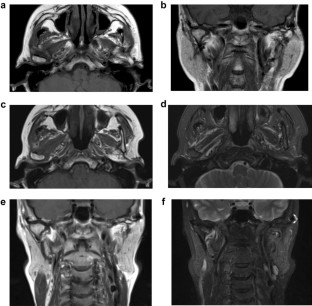

A case of tophaceous pseudogout (i.e., calcium pyrophosphate dihydrate crystal deposition disease) in the temporomandibular joint (TMJ) extending into the cranium is reported. A 59-year-old woman was referred to hospital with swelling and pain in the left cheek, and with trismus. Computed tomography imaging revealed a large, granular, calcified mass surrounding the left condylar head, partly destroying the cortex of the condylar head, and extending into the cranium by destroying the glenoid fossa. Magnetic resonance imaging revealed that the soft-tissue mass was of low-signal intensity on T1- and T2-weighted images, and was enhanced after intravenous injection of gadolinium. The mass was clinically and radiographically suspected to be a neoplastic lesion or a synovial osteochodromatosis. However, histological analysis demonstrated that the mass contained granulomatous lesion due to multiple nodular deposits of numerous rod-shaped and rhomboid crystals, which verified the diagnosis of tophaceous pseudogout. The lesion was excised surgically using a preauricular approach. Neither radiographic nor clinical examination demonstrated any signs of mass recurrence in the long-term 8- and 14-year postoperative recall examinations. Tophaceous pseudogout is a rare benign arthropathy that presents with clinical and radiographic features mimicking neoplastic conditions of the TMJ. Therefore, it is recommended that tophaceous pseudogout is considered in the differential diagnosis when a calcified mass lesion of the TMJ is encountered.

Fig. 2